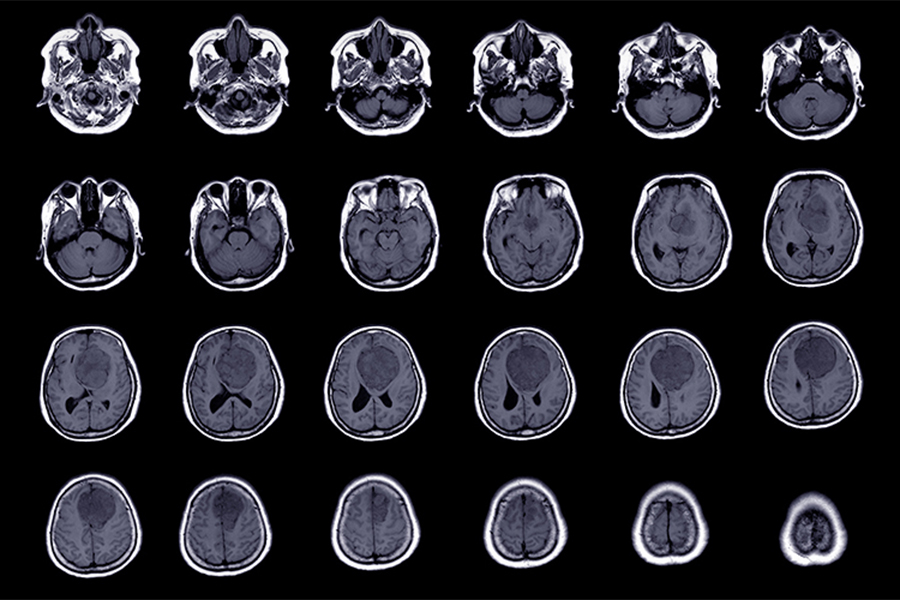

Until now, adding rare molecular features to the criteria used to grade CNS tumours or using alternative classifications has failed to offer a practical way to improve outcome prediction in most patients with meningioma. (Photo: Getty Images)